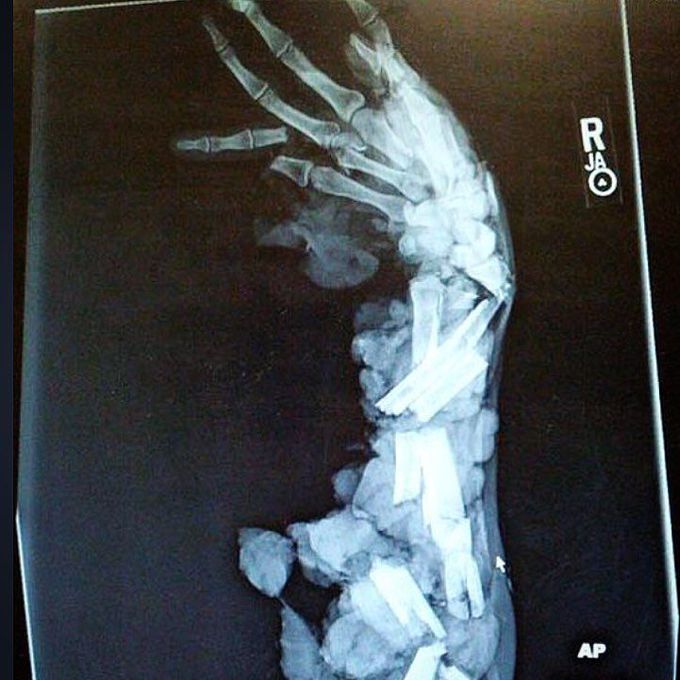

X-Ray of a man who got his arm and hand stuck in a meat grinder, causing a diffuse injury and varying degrees of deformity.